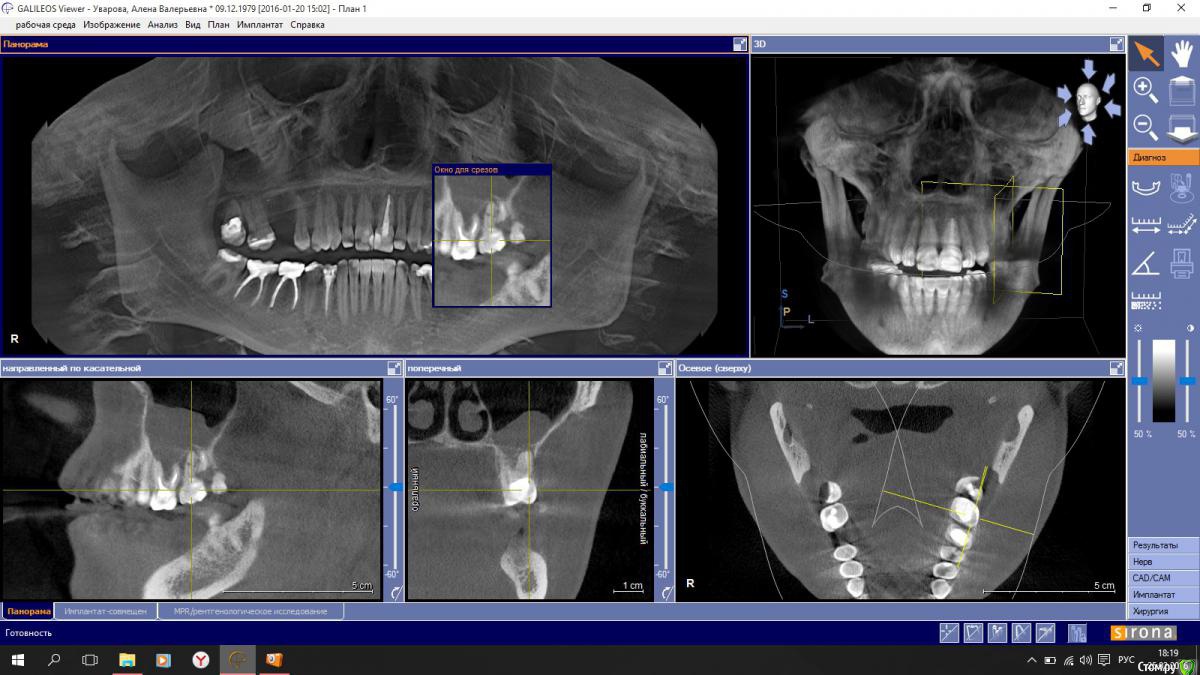

снимок показал воспаление в гайморовой пазухе слева, на ваш профессиональный взгляд 27 зуб следует удалить , как источник инфекции?

или можно его вылечить?

post-46817-0-49829900-1456415880_thumb.jpgpost-46817-0-08447500-1456415884_thumb.jpg